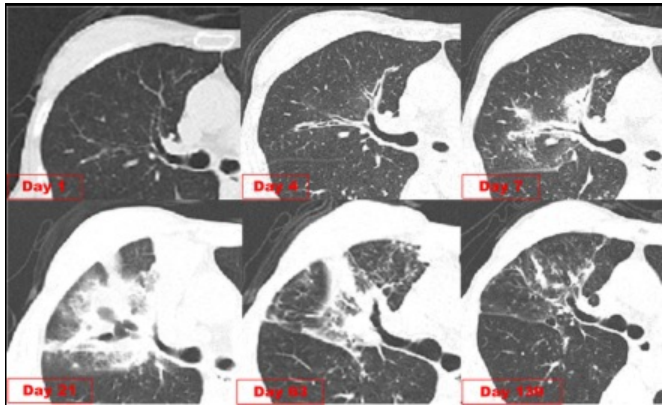

IAPA在发展过程中,较早可出现咳嗽、咳痰,进而出现呼吸困难、呼吸衰竭、缺氧性ARDS,进展迅速,即使气管插管、建立人工气道,患者也常出现气道峰压逐渐升高、潮气量逐渐下降,常因呼吸衰竭而无法挽救。但因其临床表现不特异,导致早期识别存在一定困难。(1)气管-支气管侵袭征象:沿支气管分布的结节及斑片影。对于没有基础疾病的重症流感病毒性肺炎患者,粒细胞数量正常,在曲霉感染后肺组织内会出现白细胞介导的强烈的炎症反应,导致渗出性支气管炎、支气管或肺泡受损及出血坏死,但直接侵袭血管的曲霉丝较少且主要以非增殖状态存在,因此多出现弥漫全肺的非特异性气道受侵型表现,而血管受侵型表现少见。如下图所示,第1天,支气管壁似乎有轻度增厚。病情进展至第4天,支气管壁明显增厚。随后迅速发展为支气管周围炎,并沿支气管侵袭、播散。图源:Respirol Case Rep, 2016, 4(1):32-34.注:双下肺实变,沿支气管血管束分布的实变、空洞,斑片状渗出影。注:支气管壁增厚、树芽征和沿着支气管血管束分布的实变。(2)对于免疫抑制宿主,可出现典型的曲霉感染影像学表现,例如实变与空洞伴晕征、空洞内有丝状结构及悬浮结节。注: A图见多叶肺炎和严重的小叶中心性、节旁性肺气肿; B图见右肺中叶空洞性浸润, 右肺下叶致密实变。图源:Chest, 2021, 160(2):e181-e184.注:A图可见实变、空洞,空洞内见丝状结构及悬浮结节;B图可见空洞、空气新月征。IAPA一种特殊的类型——侵袭性气管支气管炎,在支气管镜直视下可见气管和/或支气管溃疡、斑块或结节、假膜,是其典型表现。图源:国际呼吸杂志, 2023, 43(4):448-453.肺活检组织、气道斑块、假膜或溃疡的活检/刷检标本中发现真菌菌丝等特征性病理表现,可作为确诊标准。此外,在痰、支气管抽吸物、支气管肺泡灌洗液(BALF)中找到曲霉菌丝也可作为临床诊断标准。图源:Lancet Respir Med, 2018, 6(10):782-792.注:支气管活检组织病理显示有坏死物质和真菌成分,菌丝呈分枝状。图源:Chest, 2021, 160(2):e181-e184.图源:Tuberc Respir Dis (Seoul), 2014, 77(3):141-144.半乳甘露聚糖(galactomannan,GM)是曲霉特有的细胞壁多糖成分。菌丝生长时,半乳甘露聚糖是最早释放的抗原,是早期检测曲霉感染的经典方法。主要包括血清GM试验和BALF GM试验。血清GM试验在非粒细胞缺乏患者敏感性较低,仅为50%左右;ICU IPA患者的血清GM试验敏感性仅为30%~50%。在IAPA患者中,当以0.5作为GM试验阳性阈值时,诊断率仅20%。对于非中性粒细胞减少患者,BALF GM试验比血清GM试验具有更高的IPA诊断效率。EORTC/MSG标准采用1.0作为单份BALF阳性阈值的标准,当同时联合血浆/血清GM试验阳性时,BALF标本阈值可下调至0.8。我国学者研究发现,当截断值从0.5增加到0.717时,BALF GM试验可以显著降低假阳性率。无论是2016年美国传染病学会(IDSA)发表的《曲霉病诊断和管理实践指南》,还是2017年欧洲临床微生物学和感染病学会(ESCMID)/欧洲医学真菌学联盟(ECMM)/欧洲呼吸学会(ERS)联合发表的《曲霉病的诊断和管理指南》,都提及血清曲霉特异性IgG抗体在慢性肺曲霉病中有最高的检测阳性率。但2023年Clin Microbiol Infect杂志发表的一篇文章显示,IPA组的曲霉IgG抗体水平明显高于非IPA组。采样时间为发病后1~3个月内亚组显著高于采样时间为发病后<1个月亚组,影像学出现肺部空洞性病变亚组显著高于非肺部空洞性病变亚组。经过对比发现,曲霉IgG抗体的特异性和阳性预测值显著低于BALF GM。PCR的优势在于不仅能检测出曲霉的属和种,还可通过识别CYP51A基因突变来判断是否存在三唑类耐药可能。标本选择顺序:BALF>血浆>血清,但已进行了抗真菌治疗患者的血样本PCR阳性预测值可从62%降至5%。单份PCR阴性结果可极大程度地排除IPA可能。PCR可能更适合用于可疑IAPA患者在拟行抗真菌治疗前的筛查以及治疗过程中的实时监测。mNGS优势在于覆盖能力广, 时效性好, 不受先前使用抗菌药物的影响, 并可提供病原鉴定分型、耐药基因及毒力因子分析。但其检测成本较高, 结果需要临床医生进行解读和判断, 标本选择以BALF为最佳。